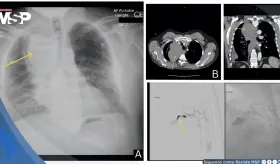

La clave estaba en entender que la tos violenta había generado una presión súbita en las arterias del cuello, causando un desgarro en la pared interna de la arteria carótida derecha.

Este caso destaca la importancia de los estudios de imagen multimodales y plantea la necesidad de reconsiderar las estrategias de detección en mujeres no fumadoras, población en la que se observa un incremento creciente de esta neoplasia.